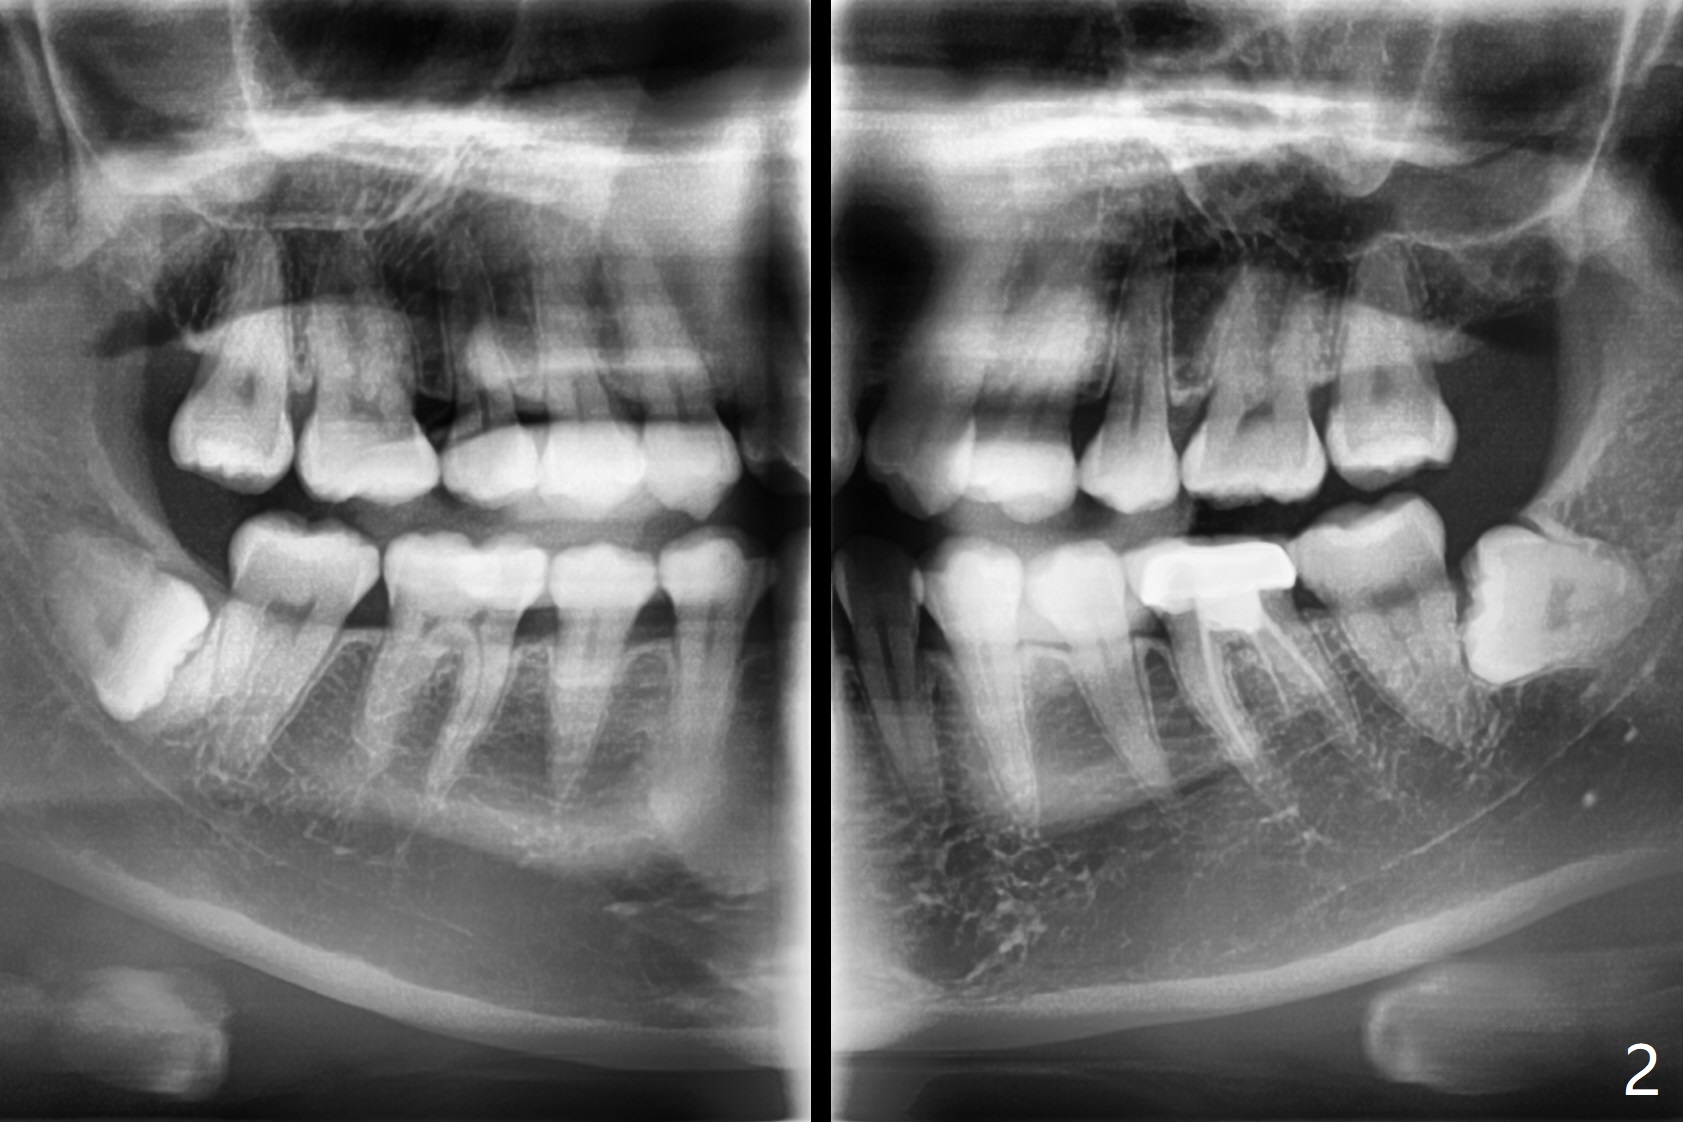

A 31-year-old woman returns with chief complaint of "occasional, mild pain in the lower left 3rd molar" 1 year post extraction of #1 and 16 (Fig.1,2). The lower 2nd molars appears to have a single fused root (Fig.2',2'' S); the radiopaque image mesial to the tooth #32 must be the dense bone (Fig.2' *). In contrast the cortex coronal to the tooth #17 is lacking (Fig.2'' v), as compared to that in Fig.2'. It seems that the bone loss at #17 is associated with mild pericoronitis. The tooth #17 should be extracted with placement of Bond Apatite to repair #18 distal defect. In fact sticky bone and collagen plug are placed instead (Fig.3), covered by 2 pieces of PRF.